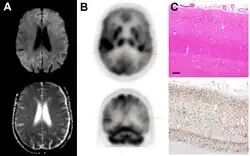

Imaging

Imaging of the brain may be performed during medical evaluation, both to rule out other causes and to obtain supportive evidence for diagnosis. Imaging findings are variable in their appearance and also variable in sensitivity and specificity.[49] While imaging plays a lesser role in diagnosis of CJD,[50] characteristic findings on brain MRI in some cases may precede onset of clinical manifestations.[51]

Brain MRI is the most useful imaging modality for changes related to CJD. Of the MRI sequences, diffuse-weighted imaging sequences are most sensitive.[52] Characteristic findings are as follows:

- Focal or diffuse diffusion-restriction involving the cerebral cortex or basal ganglia. The most characteristic and striking cortical abnormality has been called "cortical ribboning" or "cortical ribbon sign" due to hyperintensities resembling ribbons appearing in the cortex on MRI.[53] The involvement of the thalamus can be found in sCJD, is even stronger and constant in vCJD.[54]

- Varying degree of symmetric T2 hyperintense signal changes in the basal ganglia (i.e., caudate and putamen), and to a lesser extent globus pallidus and occipital cortex.[50]

Brain FDG PET-CT tends to be markedly abnormal, and is increasingly used in the investigation of dementias.

- Patients with CJD will normally have hypometabolism on FDG PET.[55]

Histopathology

Testing of tissue remains the most definitive way of confirming the diagnosis of CJD, although even a biopsy is not always conclusive.[56]

In one-third of people with sporadic CJD, deposits of "prion protein (scrapie)", PrPSc, can be found in the skeletal muscle or the spleen.[57] Diagnosis of vCJD can be supported by biopsy of the tonsils, which harbor significant amounts of PrPSc; however, biopsy of brain tissue is the definitive diagnostic test for all other forms of prion disease. Due to its invasiveness, a biopsy will not be done if clinical suspicion is sufficiently high or low. A negative biopsy does not rule out CJD, since it may predominate in a specific part of the brain.[58]

The classic histologic appearance is spongiform change in the gray matter: the presence of many round vacuoles from one to 50 micrometers in the neuropil, in all six cortical layers in the cerebral cortex, or with diffuse involvement of the cerebellar molecular layer.[59] These vacuoles appear glassy or eosinophilic and may coalesce. Neuronal loss and gliosis are also seen.[60] Plaques of amyloid-like material can be seen in the neocortex in some cases of CJD.[61]

However, extra-neuronal vacuolization can also be seen in other disease states. Diffuse cortical vacuolization occurs in Alzheimer's disease, and superficial cortical vacuolization occurs in ischemia and frontotemporal dementia. These vacuoles appear clear and punched out. Larger vacuoles encircling neurons, vessels, and glia are a possible processing artifact.[58]